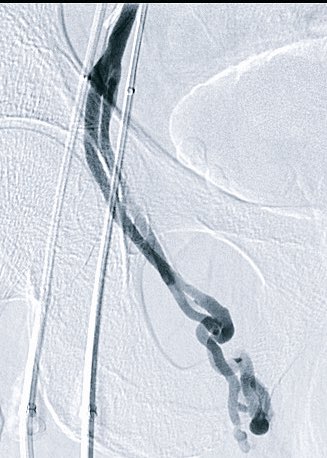

Part1- There are bleeding duodenal ulcers, and then there's this! #irad @SIRRFS @allen_herr @Cstark84 #gobbleonthis